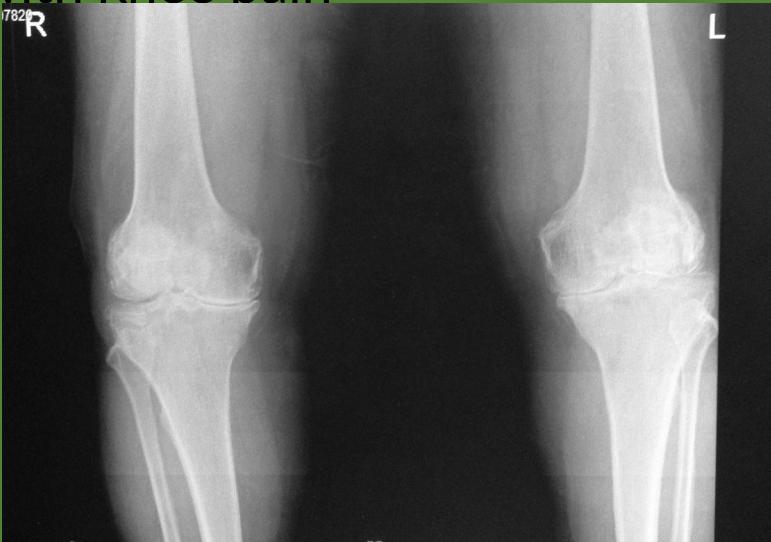

Examination of the knee

Knee Exam

https://www.youtube.com/watch?v=17ZKya9yR2Y

https://www.youtube.com/watch?v=oyKH4EYfJDM

| Item | Procedure | Purpose/ Indication … | Attachment Links | Positive Finding/Interpretation |